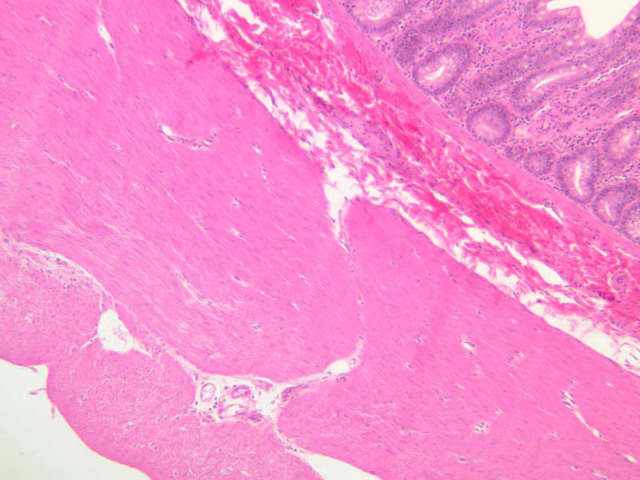

Blood passes from the elastic arteries via arteries of intermediate type into the muscular (distribution) arteries. Locate and examine a muscular artery in slide A-28 (Renal artery & vein, H&E [2.5x, 10x-labeled, 20x, 40x-labeled] [10x-labeled, 20x, 40x]; AF [10x-labeled, 20x, 40x]). Note that the tunica intima is separated from the tunica media by a thick internal elastic membrane which has a scalloped appearance. The tunica media consists of many layers of smooth muscle cells arranged concentrically in a spiral fashion (A-28, H&E [2.5x, 10x-labeled, 20x, 40x] [2.5x, 10x, 20x, 40x, 40x] [2.5x, 10x, 20x]). An external elastic membrane is present, but is thinner and less complete than the internal elastic membrane. The tunica adventitia is about equal in size to the media in this vessel and is more intensely eosinophilic in its staining properties. Note the appearance of small blood vessels in the outer part of the tunica adventitia. You may also be able to see occasional nerve fibers.

Large veins have a very narrow tunica intima and only a few layers of muscle and fibers in the tunica media (A-28, H&E [2.5x, 10x-labeled, 20x, 40x], AF [2.5x, 10x, 20x, 40x]). Its chief coat, as in smaller veins, is the tunica adventitia, but in this case, the coat is composed mostly of longitudinal muscle fibers. Some other large veins, particularly those of the cranial cavity, lack muscle and thus differ from the venae cavae. The structure of veins generally and large veins in particular is more variable than arterial structure.